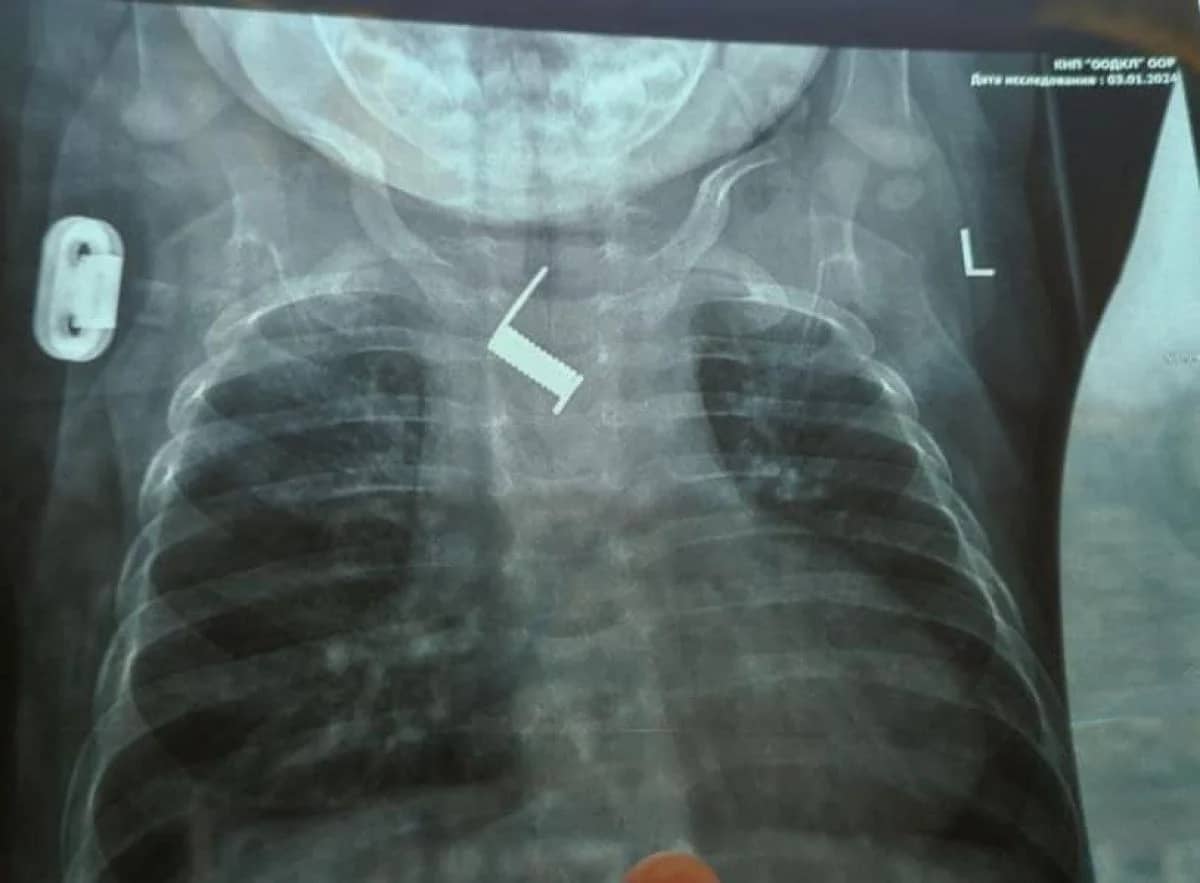

В Одесі врятували малюка з пружиною у стравоході: до того крихітку два тижні "лікували" від бронхіту

В Україні провели неймовірну операцію: як допомогли немовляті